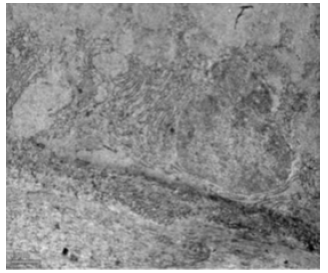

Scanning electron microscopic examination of the ileum from the control rat revealed typical leaf like villi with smooth microvillous surface (Figure 41). A prominent tongue shaped villous tip with a broad base and blunt apex was also observed in the ileum of control rat (Figure 42). In fluoridated rats, fused villi which give doughnut like appearance and Paneth cells were also present (Figure 43). The ileal mucosa of fluorotic rats revealed erosions. At the villous surface, stratified cells and some exfoliated cell sheets were also seen in several regions (Figure 44). The fluorotic ileal mucosa had fissures at the base of villi were present. The tips were curved and broken and showed signs of erosions (Figure 45). SEM examination of ileum from fluoridated rats showed corrugated appearance and the villi abruptly became stubbier, slightly curved and swollen (Figure 46).

Figure 41: Scanning electron micrograph of ileum of control rat showing leaf like villi with smooth microvillous surface. X 607.

Figure 43: Scanning electron micrograph of ileal tissue treated with 600 mg sodium fluoride for 40 days showing doughnut shaped appearance of villi (↑), caused by their indented tips and presence of paneth cells (↑). X 5000.

Figure 44: Scanning electron micrograph of ileum of rat treated with 600 mg/kg b.w./day of NaF for 40 days showing apparent erosions (↑) stratification and exfoliation of cells (↑). X 731.

Figure 45: Scanning electron micrograph of ileum of rat treated with 600 mg/kg b.w./day of NaF for 40 days showing fissures (↑) and damaged villi (↑). X 435.

Figure 46: Scanning electron micrograph of ileum of rat treated with 600 mg/kg b.w./day of NaF for 40 days showing corrugations (↑), curved and swollen villi (↑). X 606.